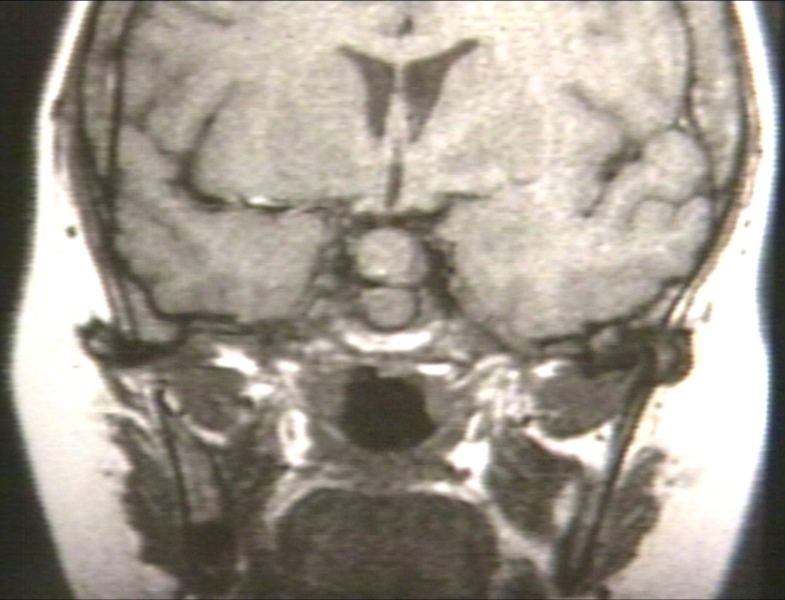

RADIOLOGY: PITUITARY: ADENOMA, PITUITARY; RECURRENT

pituitary, radiology